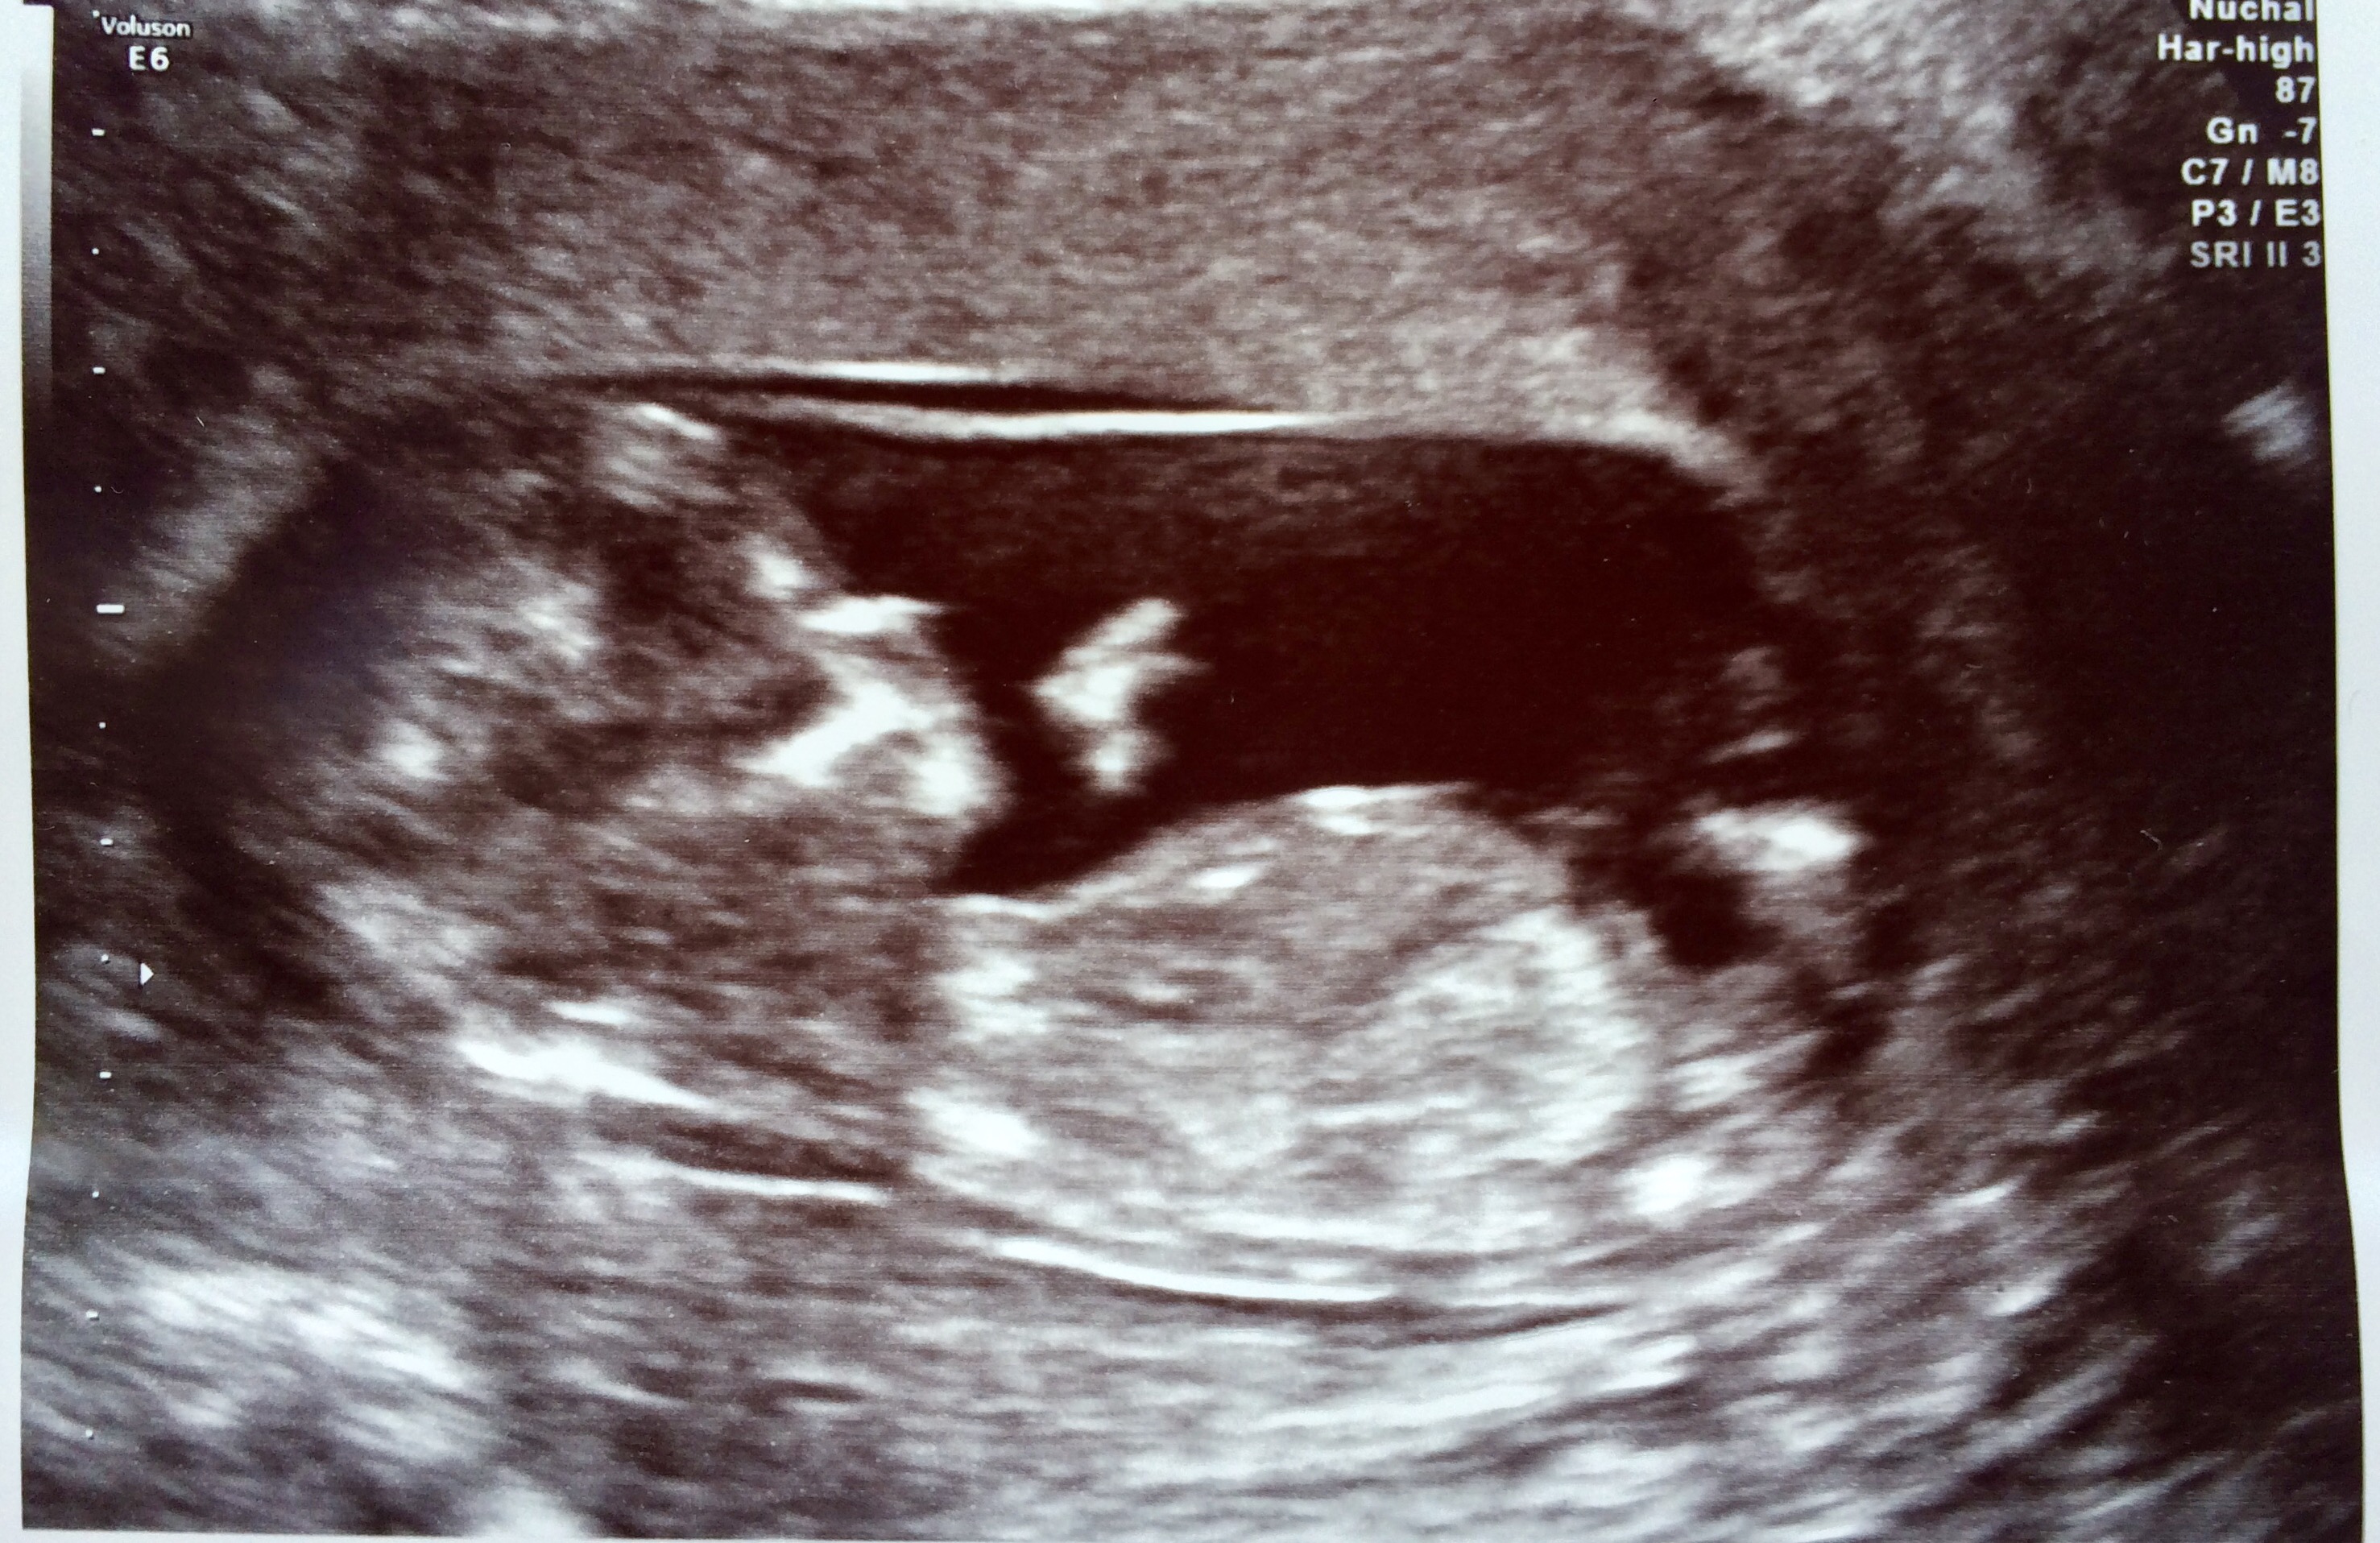

Not the best nub shot but leaning boy

More pics? Very slight boy lean.

Boy guess